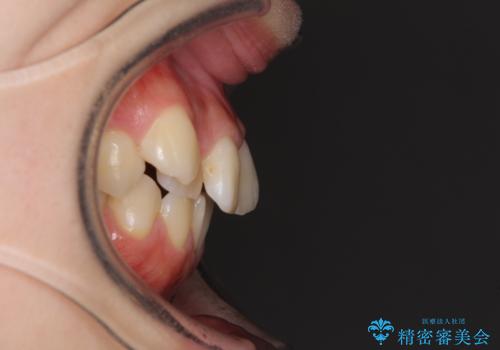

- 前歯のデコボコを気にして来院された患者様です。

本人は気づいていませんでしたが、下顎前歯が2本欠損しており、上下の歯列がアンバランスとなりデコボコになっていました。

上下のバランスを取るため、上顎左右第一小臼歯2本を抜歯し、ワイヤー矯正を行うこととしました。